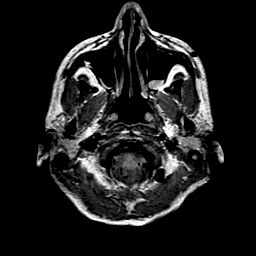

Sarcoma, MR Study #1 mr-pd -- Slice #0

[Home][Help][Clinical] Slice 0